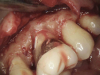

(3.) The initial surgical exposure revealed defects coronal to the crestal bone that were filled with granulation tissue and consistent with ECR.

Figure 3

(4.) The granulation tissue was removed in its entirety, and the defects were treated with a 90% TCA solution.

Figure 4

(5.) The defects were filled with a bioactive, biocompatible calcium silicate-based restorative cement.

Figure 5